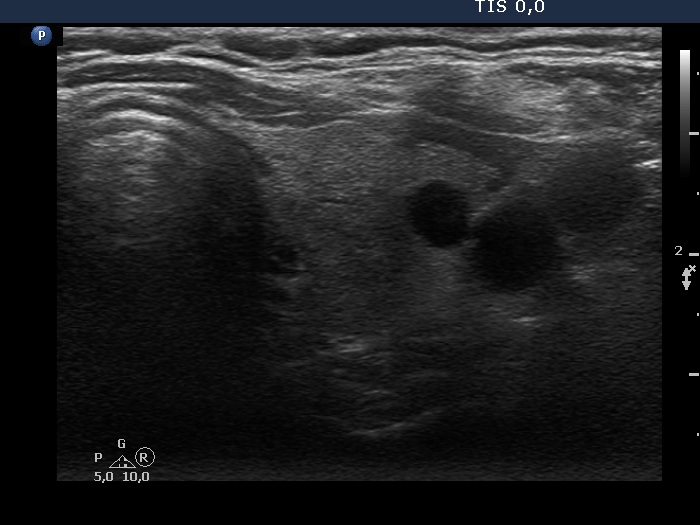

Intranodular hyperechogenic figures - case 372 (ultrasonographic picture 6)

Left lobe, trasnverse scan. This lobe is also echonormal and contains a cystic lesion in this section.